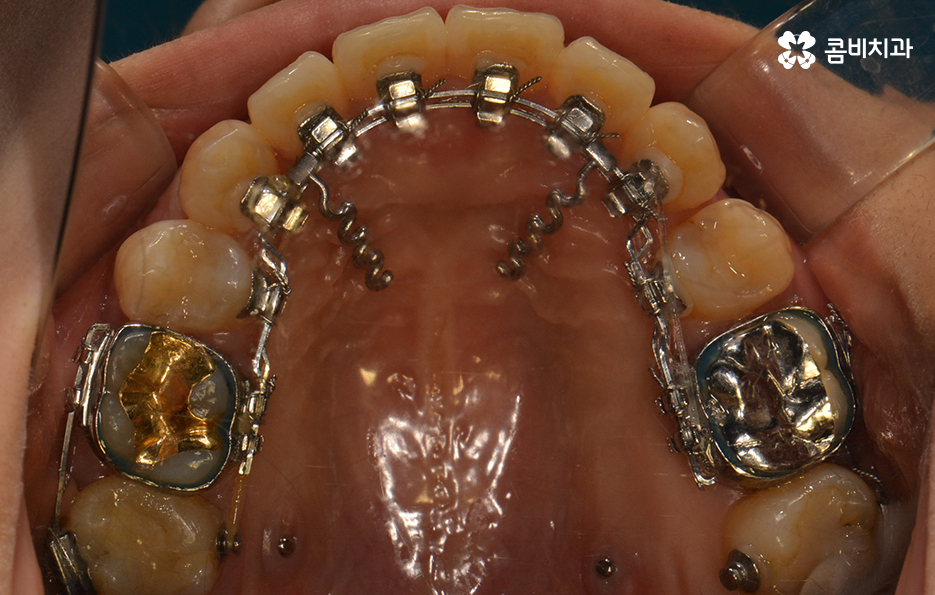

윗니가 설측으로 시술이 진행되고 있는 모습이며

발치를 한 부위 안쪽으로 치아가 이동하기 때문에

돌출입의 개선이 함께 이뤄지며 치열뿐 아니라

얼굴과 자연스럽게 어울리는 결과를 얻을 수 있습니다.

교정 치료 진행과정의 경과 모습

초기에 시술이 진행된 모습에 비해서 윗니가 가지런해졌고

돌출되었던 치아가 안쪽으로 많이 들어온 모습입니다.